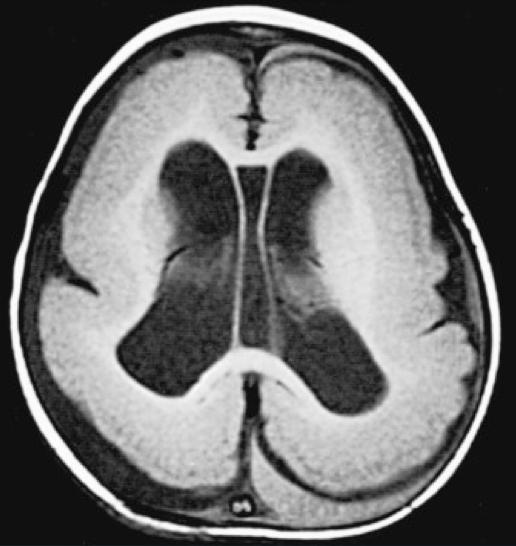

What is your Dx?

Lissencephaly (neuronal migration disorder that leads to an absence of sulci)